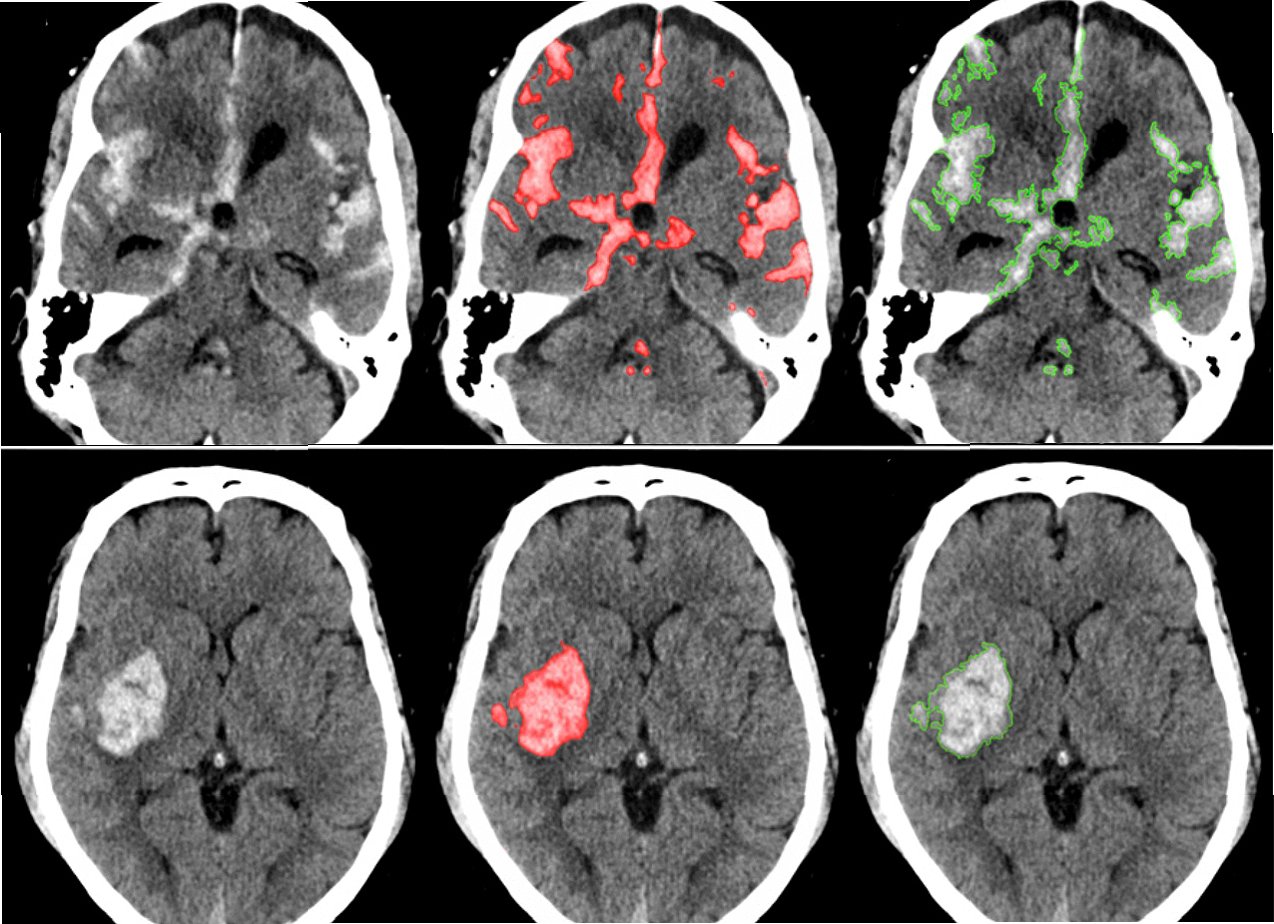

인공지능(AI) 기술은 뇌졸중 진단과 치료 분야에서 괄목할 만한 발전을 이루고 있습니다. AI 기반의 영상 분석 기술은 뇌 CT, MRI 등의 의료 영상에서 미세한 변화를 감지하여 뇌졸중의 조기 진단을 돕습니다. AI는 뇌졸중의 유형, 위치, 심각도를 빠르고 정확하게 파악하여 의료진의 의사 결정을 지원하며, 치료 계획 수립에 기여합니다. AI 알고리즘은 뇌졸중 환자의 예후를 예측하고, 맞춤형 재활 치료 계획을 수립하는 데 활용됩니다. AI 기술은 뇌졸중 환자의 생존율을 높이고, 후유증을 최소화하는 데 기여하며, 의료 서비스의 효율성을 향상시킵니다. AI 솔루션은 뇌졸중 치료의 새로운 지평을 열어가고 있습니다.

실제 의료 현장에서 AI 기반 뇌졸중 솔루션의 활용 사례가 증가하고 있습니다. AI는 응급실에서 뇌졸중 의심 환자의 CT 영상을 분석하여 뇌출혈 여부를 빠르게 판단하고, 의료진에게 신속한 치료 결정을 돕습니다. AI는 뇌졸중 환자의 재활 치료 과정을 모니터링하고, 환자의 회복 속도에 맞춰 맞춤형 재활 프로그램을 제공합니다. AI 기반의 원격 의료 시스템은 뇌졸중 환자가 거주지에서 전문적인 의료 서비스를 받을 수 있도록 지원합니다. AI 기술은 의료진의 업무 부담을 줄이고, 환자 중심의 의료 서비스를 제공하는 데 기여합니다. AI 솔루션은 의료 자원이 부족한 지역에서도 뇌졸중 환자에게 효과적인 치료를 제공할 수 있도록 돕습니다.